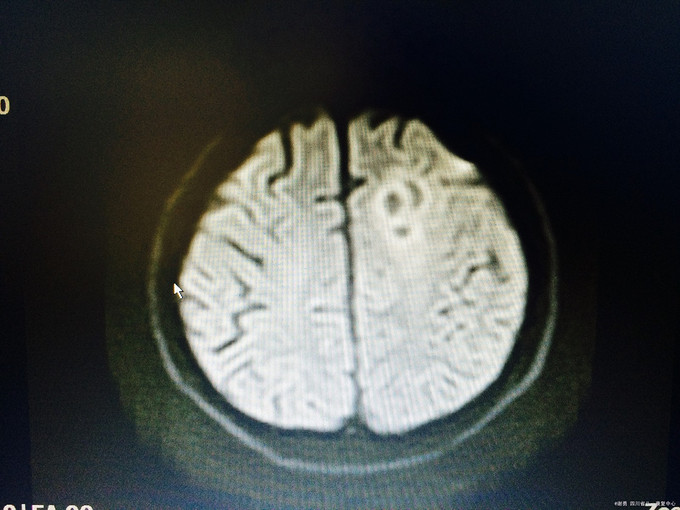

入院查体:生命体征平稳,高级皮层功能正常;四肢肌张力不高,肌力5级,病理征未引出;头颅MRI示:左侧额叶皮层下见23*15*16mm“多囊状”异常信号,见等信号囊壁,周边少许水肿信号,增强信号见病灶壁环形强化,边缘一结节状强化,肿瘤?脑囊虫病?左颞叶、顶叶、颞叶多个结节状,长T1长T2信号,FLAIR呈高信号;左颞叶见一强化“小结节”; 入院诊断:颅内占位改变,性质待定:脑膜瘤?脑囊虫病?

颅内占位疾病,定性诊断是难点:本疾病考虑脑囊虫病的支持点:亚急性起病,影像学上发现多囊状异常信号,囊壁环形强化,脑脊液提示炎性反应,不支持点寄生虫全套为阴性,但仍然需诊断性治疗;脑膜瘤,强化不支持;血管瘤?需进一步追踪、随访。